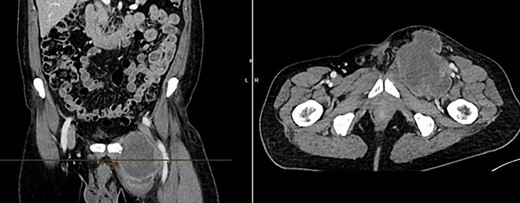

Further clarification was sought through a computed tomography (CT) scan of the entire abdomen (Fig. 1). The CT from 25 February 2022 showed an oval, encapsulated structure in the right groin area, most likely interpreted as a soft tissue hematoma. No active bleeding was observed. An enlarged lymph node was considered as a differential diagnosis. A follow-up CT on 1 August 2022 showed a size-progressive formation within the suspected right inguinal hernia compared with the previous examination in February (Fig. 2). There was no evidence of tumor recurrence or metastasis-suspect lesions intra-abdominally. A previous hysterectomy was also noted.

CT of the abdomen from 25 February 2022: oval encapsulated structure in the right groin area, most likely soft tissue hematoma, no active bleeding, DD enlarged lymph node.